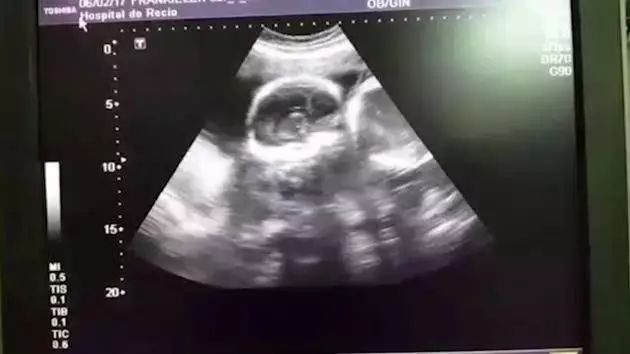

医生在看完B超后,

满脸笑容的说道:

“祝贺你们,

这是一对双胞胎!”